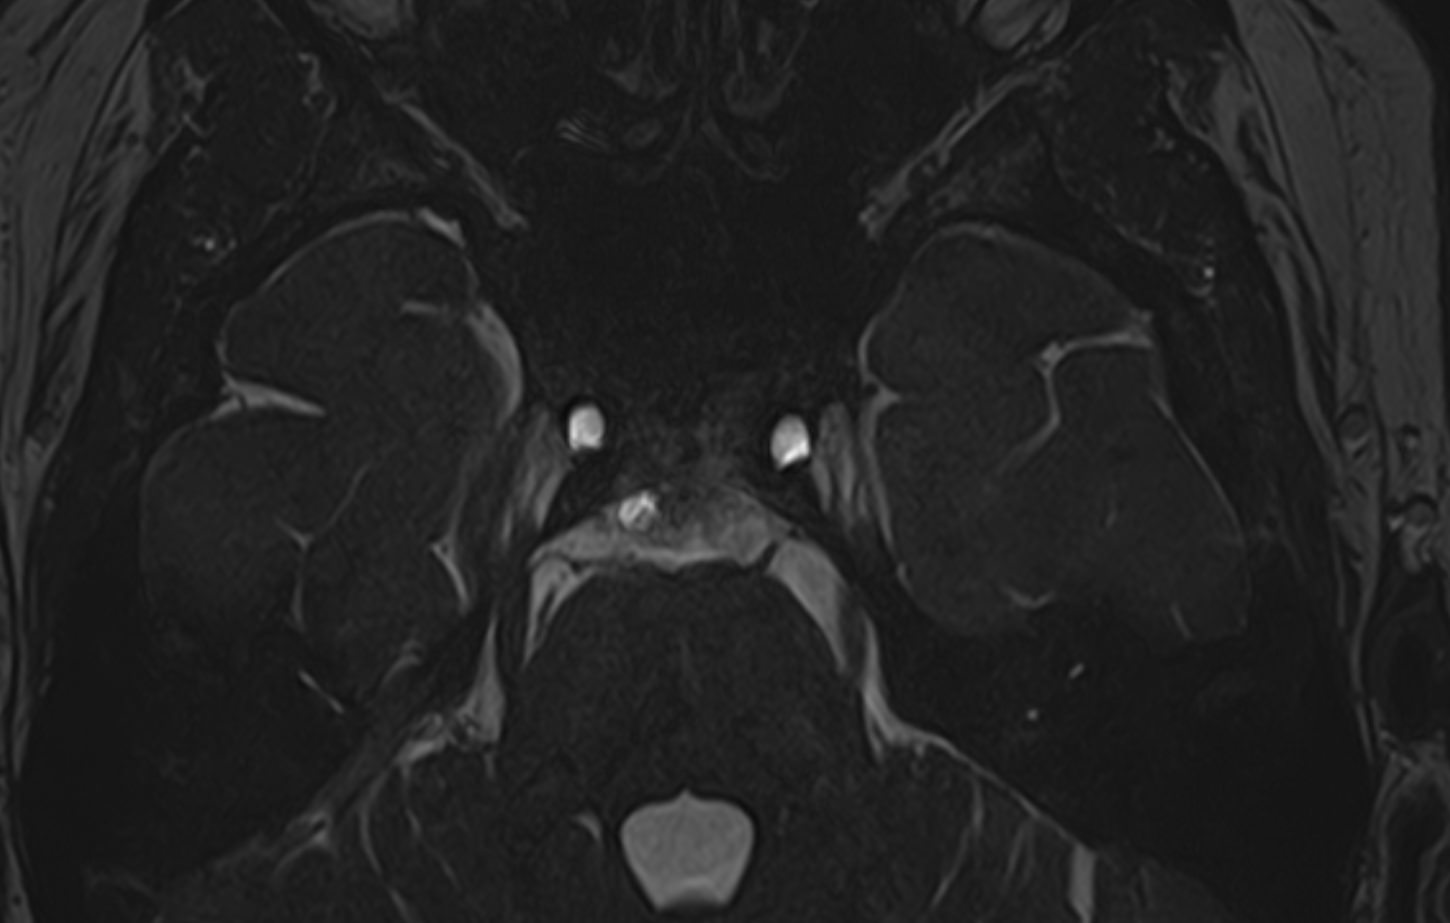

Для диагностики поражения черепно-мозговых нервов, а также оценки состояния окружающих их тканей и визуализации сосудистой сети головного мозга в клинике «Доступная медицина» проводится комплексное обследование МРТ головного мозга + черепно-мозговые нервы. Данное обследование включает в себя 2 протокола: стандартный — для оценки состояния всех структур головного мозга и специализированный — для изучения очагов поражения черепных нервов.

Оба исследования выполняются на современном высокопольном томографе экспертного класса TOSHIBA VANTAGE TITAN 1,5 Тесла, который использует разные режимы сканирования с толщиной среза от 1мм в различных плоскостях с последующей цифровой обработкой полученных данных для создания трехмерных изображений. Аппарат позволяет выявлять структурные изменения в веществе головного мозга и черепных нервах уже на начальной стадии, когда другие методы не дают результатов.

• патология нервов на фоне сосудистых проблем (вазоневральный конфликт — сдавление нерва близлежащим сосудом, также на фоне патологической извитости, аневризмы, сосудистой мальформации).